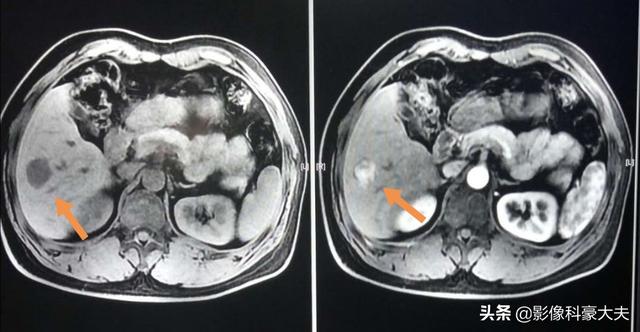

この中年男性は慢性B型肝炎の既往があり、超音波検査で肝右葉下節に不均一な低エコーを認め、臨床検査でα-フェト蛋白の上昇を認め、さらに磁気共鳴検査で古典的な丸みを帯びた低信号域を認め、増強検査で不均一な増強を認めたことから、小さな肝細胞癌であることが明らかになり、3年近く手術を受けていた。

また、典型的な病変であれば、強調CTで診断を確定することができますが、小さな肝臓がんの中には、やっかいで非典型的なものもあり、特殊な造影剤を用いたMRIによる強調検査が必要になることがあります。

プロメテウス肝拡大MRIは小型肝細胞癌の診断に重要なツールである。